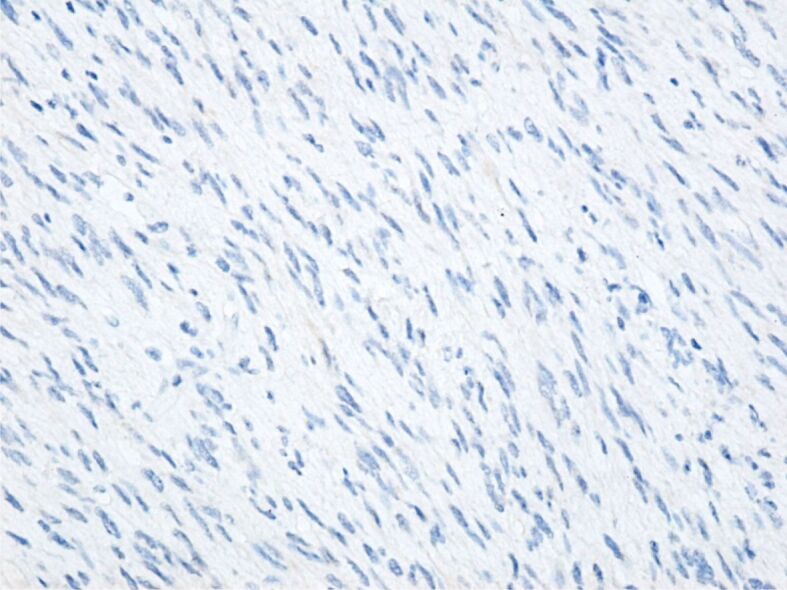

Solitary fibrous tumor (SFT) is a rare mesenchymal tumor that is quite aggressive and prone to recurrence and metastasis. Most SFTs are benign, but the identification of the histological features that define the dedifferentiation of SFTs can predict the aggressiveness of the tumor and the presence of a reserved prognosis. We present a rare case of conventional SFTs with features of malignancy and highlight the diagnostic and therapeutic difficulties related to this case. Computed tomography aspect suggested a possible gastrointestinal stromal tumor. Surgical intervention was performed through median laparotomy and a tumor of approximately 15∕12 cm was found, developed from the level of the right retroperitoneal space, and pushing anteriorly the ascending colon, cecum, and terminal ileum. The immunohistochemical aspect correlated with the histopathological one suggests a SFT most likely malignant. In conclusion, the early diagnosis of SFTs is essential in establishing an appropriate treatment. Immunohistochemistry is indispensable in establishing the diagnosis of SFTs.

Abstract Image